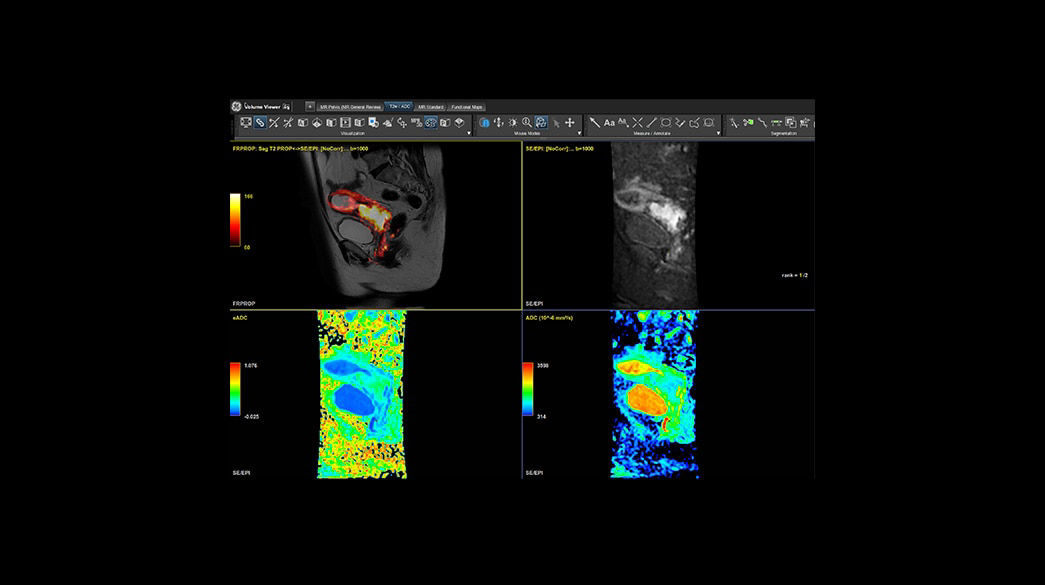

Quantifiable

Provides quantitative and actionable information

Consistent

Motion and distortion-reduced scans with high-resolution and contrast